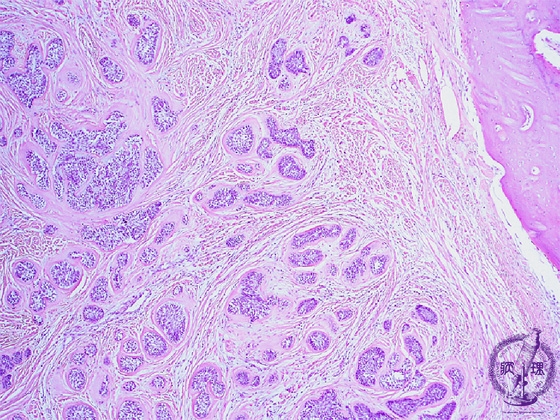

Microscopic finding (HE stain, low-power view):Multiple tumor nests proliferate in a background of fibrous stroma with bone resorption (follicular type).